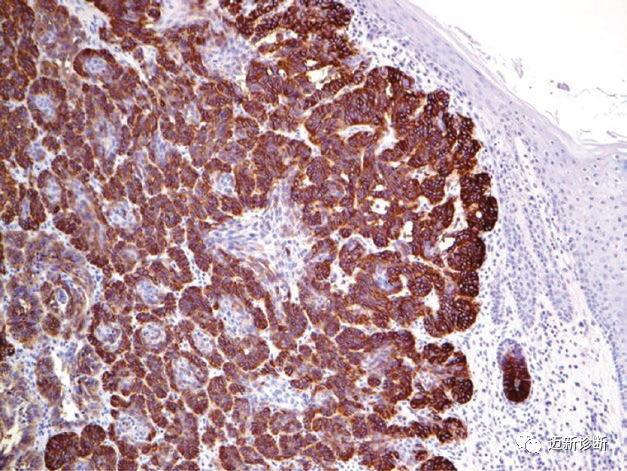

图片

图1. 基底细胞癌,EP-CAM强阳性表达。